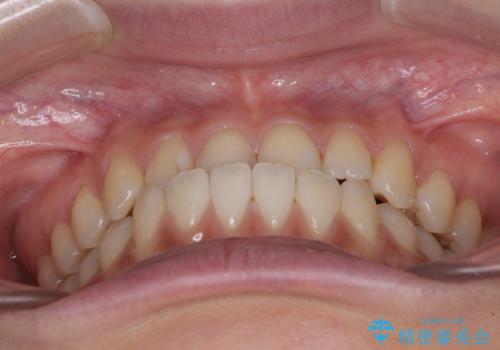

前歯のクロスバイトを治したい ワイヤー装置による矯正治療

- 前歯の反対咬合を気にして来院された患者様です。

クロスバイト改善まではスムーズに進みましたが、その後は強い舌の突出癖によりオープンバイトの期間が長く続きました。